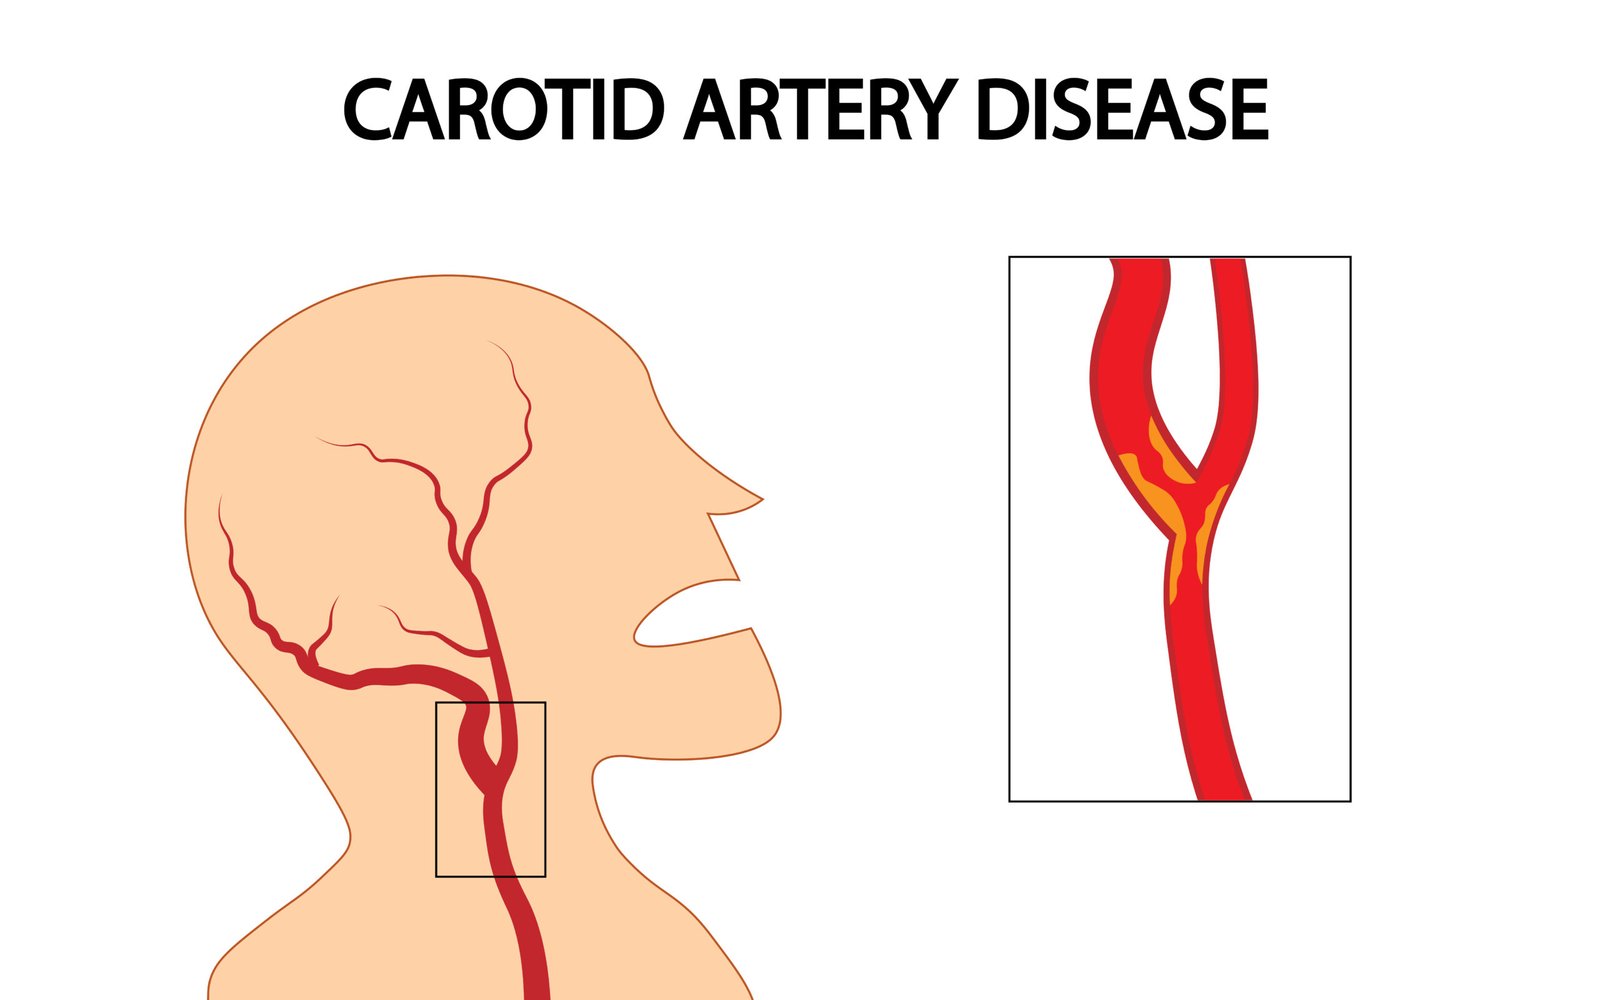

Carotid Artery Ultrasound. A carotid artery ultrasound is a painless, non-invasive test that uses sound waves to create images of the carotid arteries in the neck. These arteries supply blood to the brain, and narrowing of these vessels can increase the risk of stroke. During the test, a small transducer is placed on the neck to measure the flow of blood and detect any blockages or abnormalities.

Who should have it? This test is particularly important for individuals with risk factors such as high blood pressure, high cholesterol, smoking, or a family history of stroke.